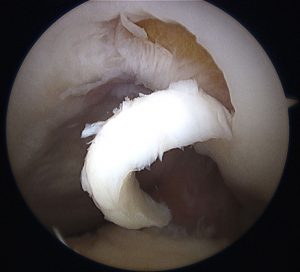

Kıkırdak yaralanmaları, diz üzerine düşmelerde, çarpmalarda veya trafik kazalarında olduğu gibi direkt veya eklemin diğer problemlerine bağlı olarak ortaya çıkabilir. Belirtiler kıkırdak yaralanmasının ağırlık derecesine göre az veya çok olabilirler. Ortak olan belirti eklemde gelişen şişlik ve ağrıdır. Belirtiler günlük yaşamdaki hareketler veya sporla artar. Ayrıca merdiven gibi yüklenmenin artığı hareketlerde ağrı artar. Şikayetlerin süreklilik göstermesi halinde teşhis ve tedavi gereksinimi doğurur. Muayene ve yapılacak radyolojik tetkikler ile teşhis konur. Son yıllarda kıkırdak problemleri MRG ve artroskopi sayesinde daha kolay ve net olarak tanımlanabilmiştir.

Kıkırdak lezyonlarında hangi tedavi yöntemi seçilirse seçilsin, önce problemin yeri, derinliği, sınırları çok iyi belirlenmeli, sınıflandırmaya göre evrelendirilmeli ve ondan sonra seçilen yönteme göre tedaviye geçilmelidir. Bu verilere göre ameliyatsız ve ameliyatlı tedavilere yönelebilinir. Günümüzde cerrahi tedaviler problemin büyüklüğü ve özelliklerine göre artroskopik olarak kıkırdak yüzeyin traşlanması, abrazyon artroplastisi, subkondral delme, mikrokırık, osteokondral otogreftleme, osteokondral allogreftler, çatı implantları ve skafoldlar, kondrosit kültürü ve transplantasyonu seçeneklerinden biri veya kombinasyonları ile sağlanmaktadır.